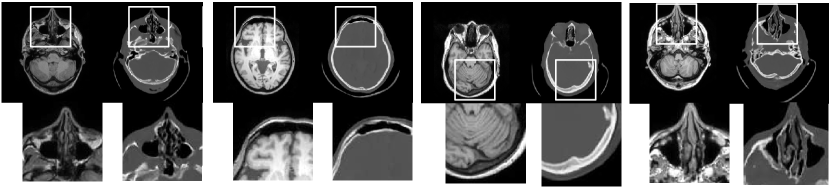

4.4 Qualitative Evaluation

In Figure 5 we analyze the prediction quality of our and compared approaches in a qualitative way. Considering modality propagation in MRI, we see that usage of uncertainty-aware patch invariance (UAPI) gives a better detailed weighting of the cerebrospinal fluid in the middle of the brain. In general, employing patch invariance yields better preservation of fine structures. This observation also applies to accelerated MRI enhancement. In particular, CUT and UAPI provide comparatively sharper knee images with more high-frequency details than the other methods.

Qualitative evaluation plays an important role for the third investigated application, namely MRI-to-CT synthesis, where quantitative comparison is not possible due to lack of ground truth data. Satisfying results were obtained with the UAPI method, which are visualized in Figure 6. Cavities and brain shapes are well preserved by our method although we used two completely independent and unaligned head datasets for this experiment. UAPI synthesizes brain table artifacts that are also visible in CQ500. A proper evaluation on cleaned CT data is necessary and thus will be considered as a future working step.